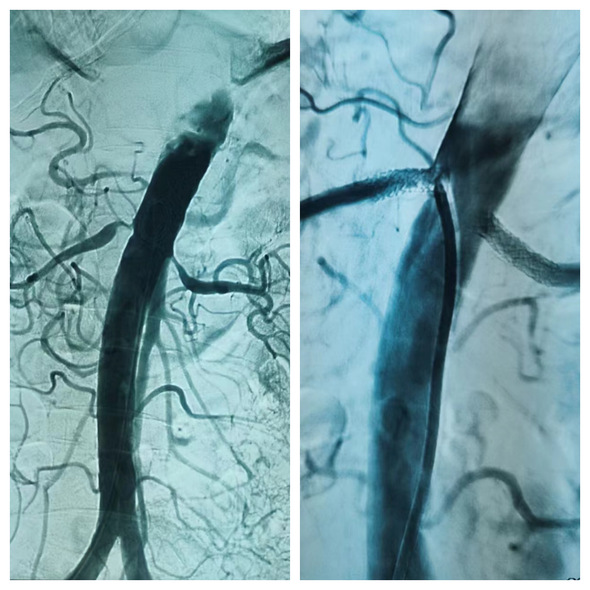

神经内五科迟景宏主任与介入科刘琳主任沟通,决定为患者行肾动脉造影检查及介入治疗。前期在病房完善相关检查化验,给予患者抗血小板聚集治疗,稳定斑块治疗。患者状态允许后,于8月28日转入介入科,当天行肾动脉造影检查,术中显示双侧肾动脉起始段重度狭窄,术后于两侧肾动脉分别植入一枚支架,血流恢复通畅。

支架前,双侧肾动脉起始段狭窄 支架后,双肾动脉狭窄解除

患者术后第一天血压降至133/71mmHg,逐渐减量口服降压药物,于术后第二天成功出院。